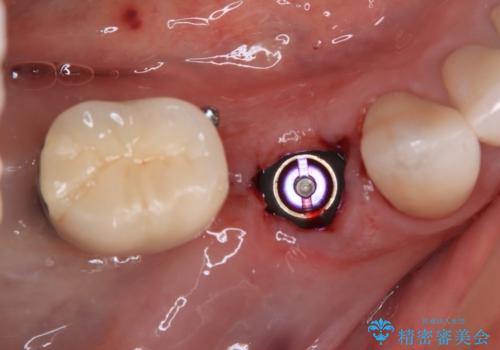

- 奥歯が割れてしまい、抜歯が必要となった患者様です。

以前にも歯が割れてインプラント治療を行いましたが、抜歯してからインプラント埋入→仮歯装着までに半年以上を要し、その間に残された歯への負担が大きくなり、左右反対側のセラミッククラウンが破折したことがありました。

そのため、当院に新しく導入した手法により、抜歯をした日にインプラントを埋入し、そのままを仮歯を装着することで、他の歯への負担を軽減する計画を立てました。

インプラント埋入時に植立具合の安定性を測定したところ、十分な数値が得られたため、速やかに仮歯を装着して咬合回復をさせることができました。